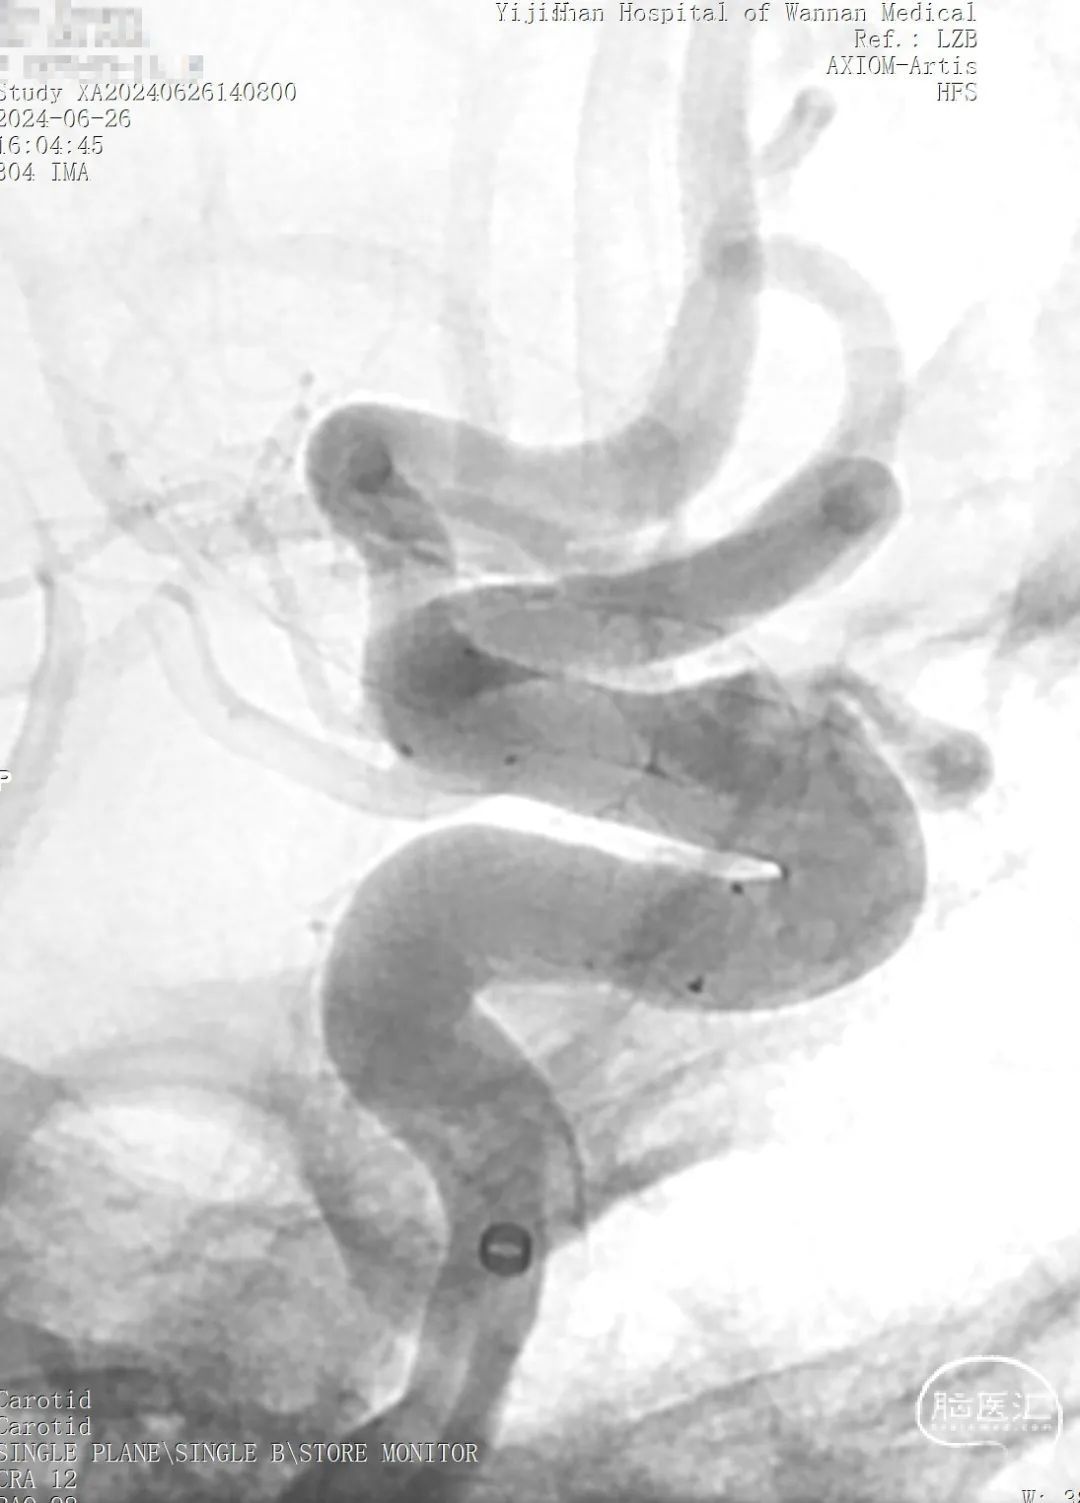

➢ 术前造影

迂曲段通桥麒麟™血流导向密网支架释放过程。

支架twist或打开不良处理。

术后血管造影见动脉瘤仍有显影,瘤腔内造影剂滞留,支架展开,贴壁良好,载瘤血管血流通畅,手术顺利。